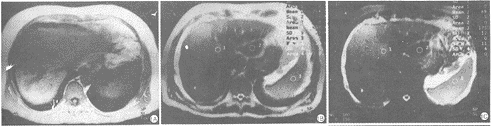

图1 块状型HCC伴肝内转移。A.FLASH-T1WI示癌肿呈低信号,边缘清。

B.HASTE-T2WI示肿块呈稍高信号,边缘较模糊,癌肿和脾脏的rCNR为0.51,0.79。

肝左叶边缘受胃网膜脂肪干扰而显示欠清晰。C.HASTE-IR-T2WI示肿块呈高信号,与肝实质对比清晰,癌肿和脾脏的rCNR为0.94,1.52。肝脏边缘清晰锐利

在HASTE序列T2WI显示肝脏结构及边缘稍模糊,肝实质病灶边缘也欠清晰,特别是肝脏与腹腔脂肪的接触面;同时脾脏周围腹腔脂肪之高信号亦干扰了其边缘的锐利。而在HASTE-IR序列上,癌肿、肝实质及肝边缘结构清晰,特别是在肝脏左叶因胃网膜脂肪信号抑制显示更加清楚(图1、2)。另外,HASTE-IR序列发现了12个(19.4%)HASTE序列没有显示的直径小于2mm的病灶,大部分分布在肝脏左叶外段和近肝门区(图3、4)。在屏气下T2WI上,HASTE和HASTE-IR序列所检测的肝脏、脾脏和肿瘤的SNR、CNR较高,均能反映肿瘤/肝实质的信号特征,但二者间的SNR和CNR值又存在差别,肝脏的SNR值HASTE序列显著性高于HASTE-IR序列(t=2.45,P=0.007)。而脾脏的SNR、肿瘤/肝实质和脾脏/肝实质的CNR,二种序列间的统计学差异又不明显(P=0.34,0.36,0.87>0.05)。但是,我们通过比较肿瘤和脾脏的rCNR这一特异性指标发现,HASTE-IR序列(TE=64ms,TI=150ms)检测的肿瘤/肝实质和脾脏/肝实质rCNR明显高于HASTE序列,两者之间的rCNR具有显著性差异(t=1.94,2.35,P=0.03<0.05)。